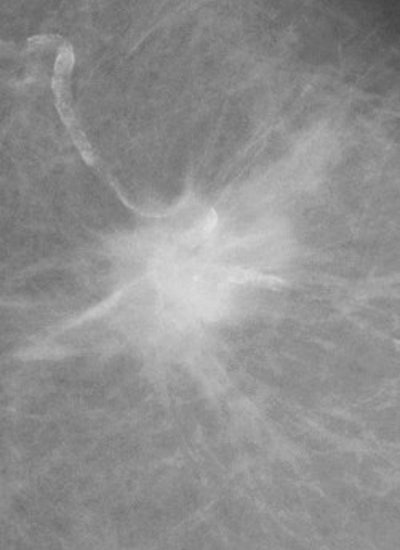

DSPM images acquired on the Mammomat 3000 Nova, including zoom (middle) and spot magnification (below). Images courtesy of Dr. Wolfgang Matzek.